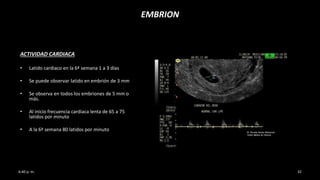

ACTIVIDAD CARDIACA

• Latido cardiaco en la 6ª semana 1 a 3 días

• Se puede observar latido en embrión de 3 mm

• Se observa en todos los embriones de 5 mm o

más.

• Al inicio frecuencia cardiaca lenta de 65 a 75

latidos por minuto

• A la 6ª semana 80 latidos por minuto

EMBRION

• A la 7ª semana 135 latidos por minuto

• A la 8ª semana 170 latidos por minuto.

FCF valorable en el 100% de los casos tanto

transabdominal y trasnvaginal

• Su máximo a la 9ª semana entre 180 a 185

• Al final del periodo embrionario entre 150-

160 latidos por minuto

• Al inicio del periodo fetal 140 latidos por

minuto (14ª semana LCC de 70-75 mm)